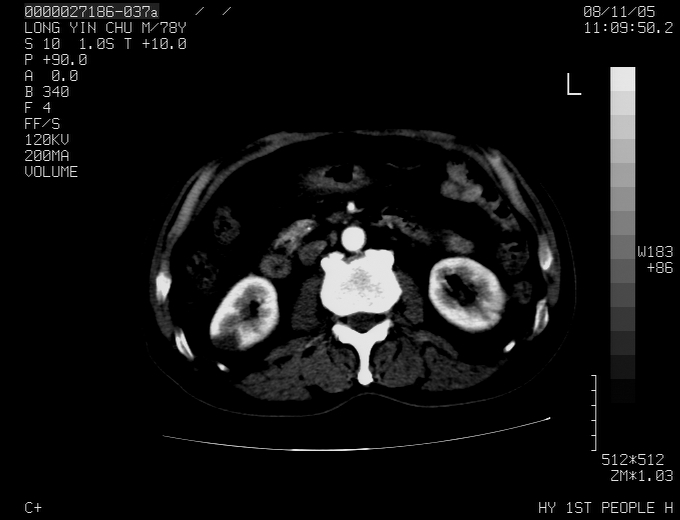

标题: CT16532:M78Y,肝脏病变,请会诊

腹胀,腹痛就诊,男性,78岁,外院b超未见异常。

考虑弥漫性肝癌并脾及双肾转移.双侧胸水.

图片质量欠佳:多考虑:左侧肾癌。脾脏转移!胸膜转移!

肝脾肾转移瘤可能性大,左肾不除外梗塞,双侧胸水

考虑肝癌并双肾及脾脏转移;双侧胸腔积液。